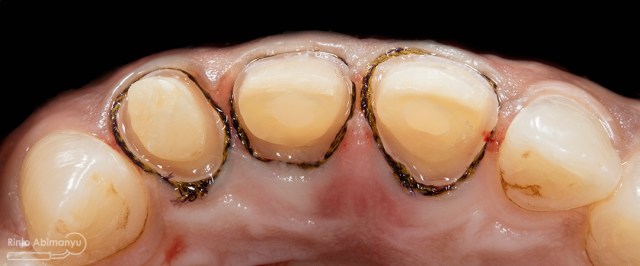

ini hasil preparasi gigi-giginya…

Hasil preparasi tampak oklusal